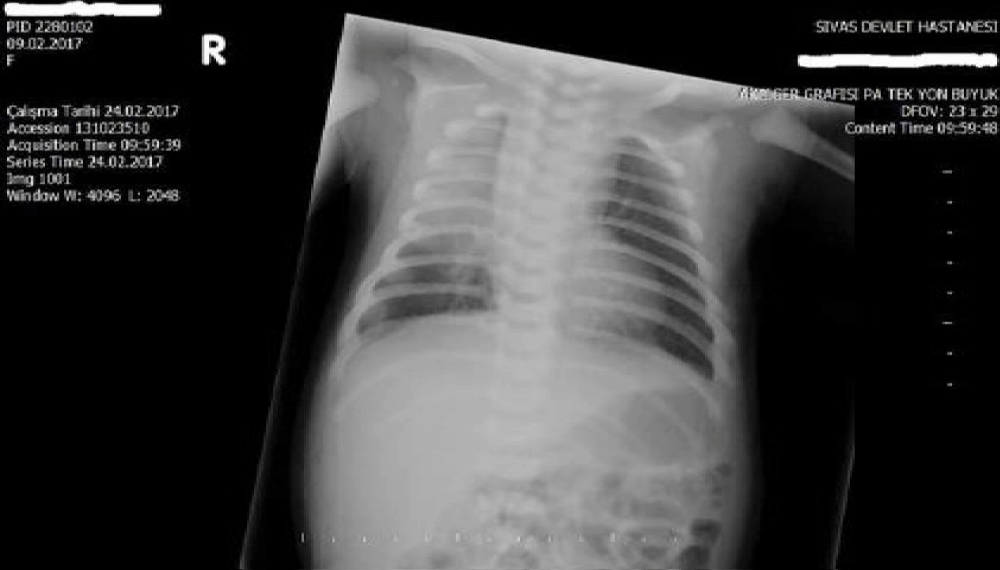

Laboratory values were unremarkable. Blood count, serum electrolytes, renal function, liver function, and blood glucose were within the normal range during the observation period. Plasma ammoniac level was 48 micmol/L. Blood level of brimonidine could not be measured as it was not available. Urine or serum toxicology screens were not performed to rule out other intoxications due to unavailability. Meningitis was not considered and lumbar puncture was not performed because infection markers were negative and clinical signs were associated with an inadvertent drug. Blood culture was negative. Chest radiograph showed consolidation of the right upper lung, which was considered to be pneumonia (Figure 1).

Figure 1: Chest X-ray shows right upper consolidation of the lung.